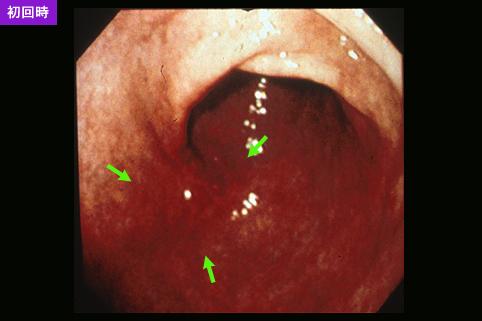

Criteria of Hist.ClassificationMalignant epithelial tumor/Signet-ring cellcarcinoma

LocationStomach/Antrum

Technique, MethodEndoscopy

Macroscopic TypesType 0/IIc (IIc) Superficial depressed type

Size20 - 24